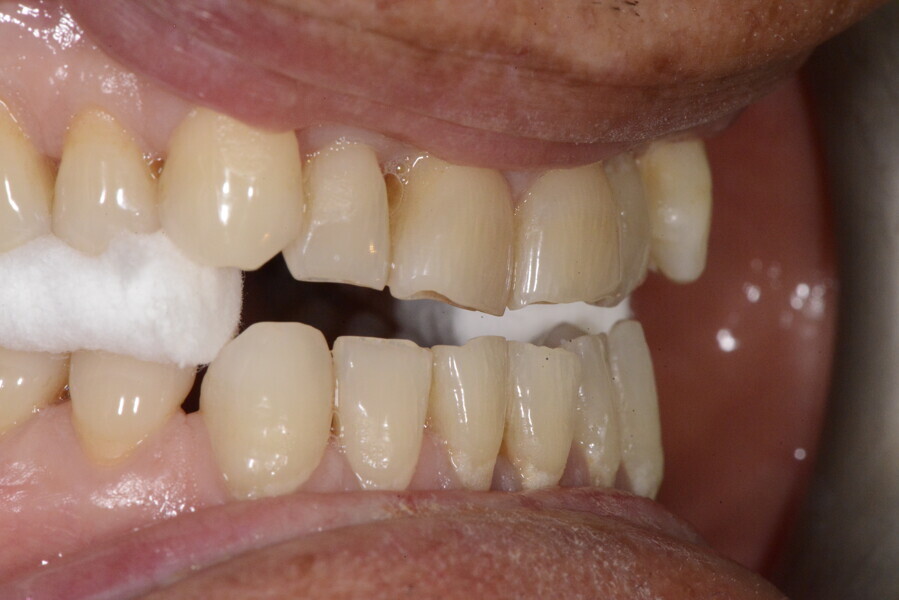

After the first phase of aligner treatment, we had achieved better inter-arch coherence, better maxillary arch expansion, and some space for improving the anterior tooth proportions restoratively (Fig. 19). We then temporarily restored the anterior teeth directly with composite, closing the spaces, improving the tooth proportions and further increasing the maxillary arch expansion (Fig. 20). We used restorative arch expansion to reduce the orthodontic destabilisation of the teeth to achieve the correct inter-arch coherence and retain the teeth in the cortical bone.38 A refinement aligner phase was undertaken to improve the final alignment of the gingival zenith and to improve the inter-arch coherence (Fig. 21). The periods of the first orthodontic phase and of the refinement were used to augment the mandibular and maxillary bone and to place the implants (Fig. 22). At the end of the orthodontic treatment, the case was finalised with ceramic veneers in the anterior area and temporary restorations on the implants in the posterior area (Figs. 23–26).

The provisional phase of about four months was important to allow the peri-implant tissue to mature and to teach the patient to chew correctly with chewing gum, cotton rolls and silicone masticatory sticks. This is fundamental training for the patient to achieve the correct alternating unilateral masticatory cycle needed to obtain the ideal rehabilitation of the masticatory system. We wanted the patient to achieve ideal masticatory and swallowing function. After sufficient rehabilitation time, we finalised the case with posterior zirconia crowns screwed on to the implants (Fig. 27).26

For maintenance purposes, after prosthetic finalisation, the patient was to carry on with the Froggymouth therapy and to use the Ri.P.A.Ra. for physiotherapeutic exercises and mastication training (Fig. 28). It was strongly recommended that the patient wear a mandibular occlusal splint during sleep. This occlusal splint was designed with disclusion guides to advance the mandible and ensure balanced contralateral support (Fig. 29).11, 39 We achieved an aesthetic appearance with adequate inter-arch coherence and a better cephalometric result (Figs. 30 & 31).